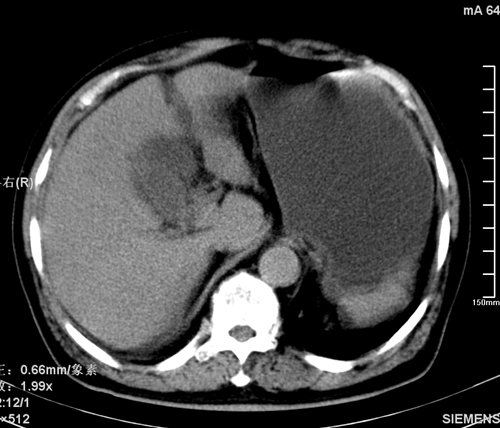

以下是引用liaoqiang在2008-3-27 15:57:00的发言:[br]1右肾脏周多发大小不一球形影,考虑肾脏囊肿可能性大。2胆囊边界欠清楚。考虑胆囊炎可能性。

以下是引用随光逐影在2008-3-27 16:33:00的发言:[br]考虑为:1)双肾囊肿可能。2)急性胆囊炎。建议:行进一步检查。